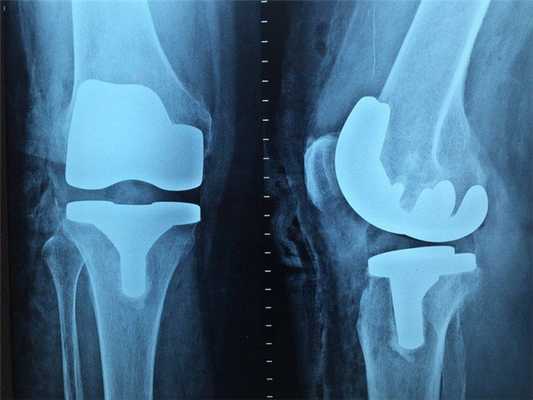

Особенности проведения МРТ при онкологии

Диагностическая процедура безболезненна и обычно длится 30-60 минут, в зависимости от области интереса. Особенной подготовки не требуется. Важно информировать врача о перенесенных операциях, установленном оборудовании: кардио-, мио-, нейростимуляторах, постоянных протезах, помпах для подачи лекарств, металлических имплантатах и пр.